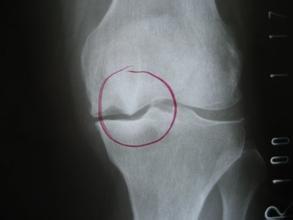

骨质增生一般不会引起症状,所以不能说疼痛就拍片,然后发现有骨质增生就一口咬定它就是疼痛的原因、把它当成病,那可是会导致误诊误治的。

只有增生的骨刺刺激到了局部组织或周围神经而产生症状的时候才叫骨质增生病。

真正的骨质增生